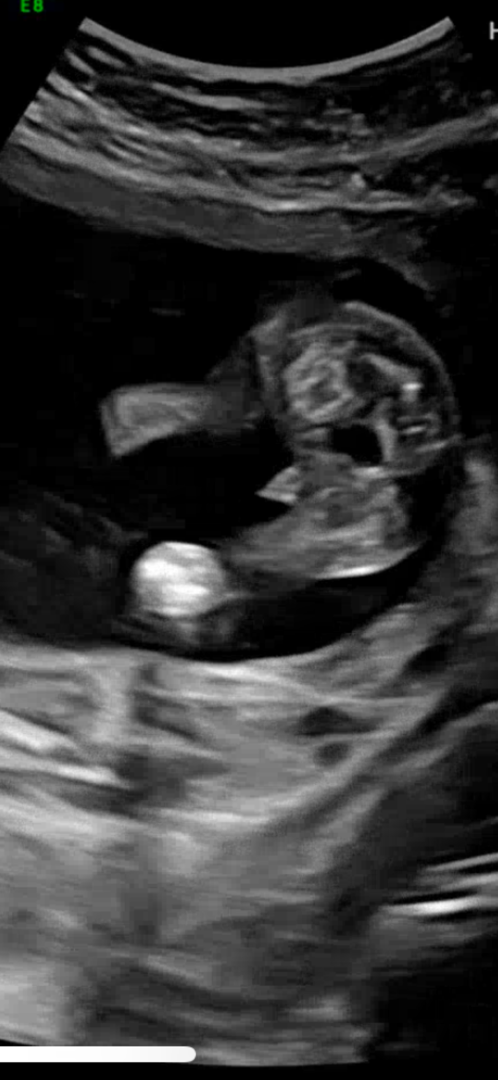

16주4일 초음파 다리 가운데 너무 뾰족

다리 사이에 고추 같은데 너무 뾰족하고 한쪽으로 쏠려있어서요.. 보시기에 어떠세요?

아마 초음파 비추는 각도 때문에 그런 듯 해요ㅎㅎ저의 아가도 뾰족한데 남아입니다~